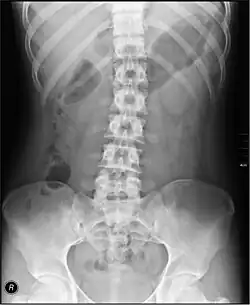

- Lumbar Spine - AP and Lateral +/- L5/S1 view in the UK, with obliques and Flexion and Extension requests being rare.[15] In the US, basic projections include an AP, two Obliques, a Lateral, and a Lateral L5-S1 spot to better visualize the L5-S1 interspace. Special projections are AP Right and Left bending, and Laterals with Flexion and Extension.

- Pelvis - AP only in the UK, with SIJ projections (prone) on special request.[15]